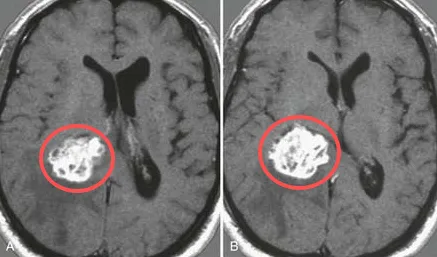

怀疑脑转移瘤需要手术吗? 转移瘤是成人常见的颅内肿瘤,占所有颅内肿瘤的一半以上。脑转移瘤是由起源于另一个器官的肿瘤细胞通过血液到达大脑而引起的肿瘤。脑转移瘤最常见的原发肿...